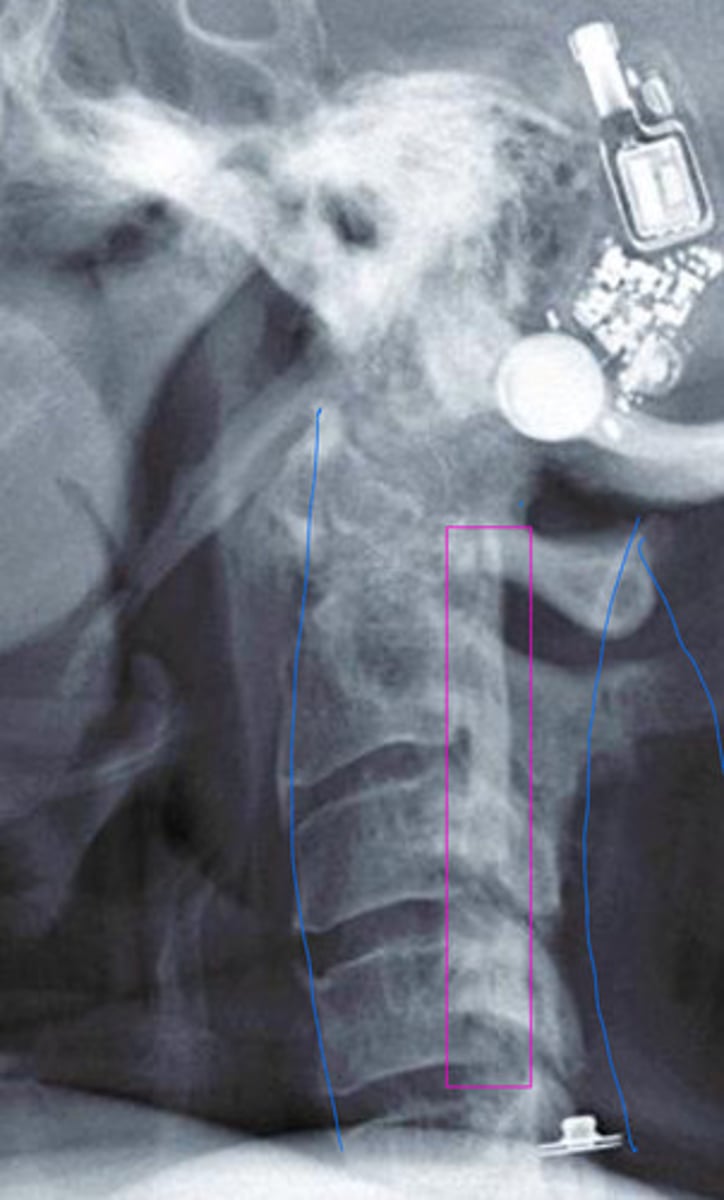

Calcification of the posterior vertebral line

Looks like fracture, not actually

What is the blue?

What is the red?

Sclerosis of the posterior vertebral line

What is the pink?

DISH (mid body to mid body)

What is in the red?